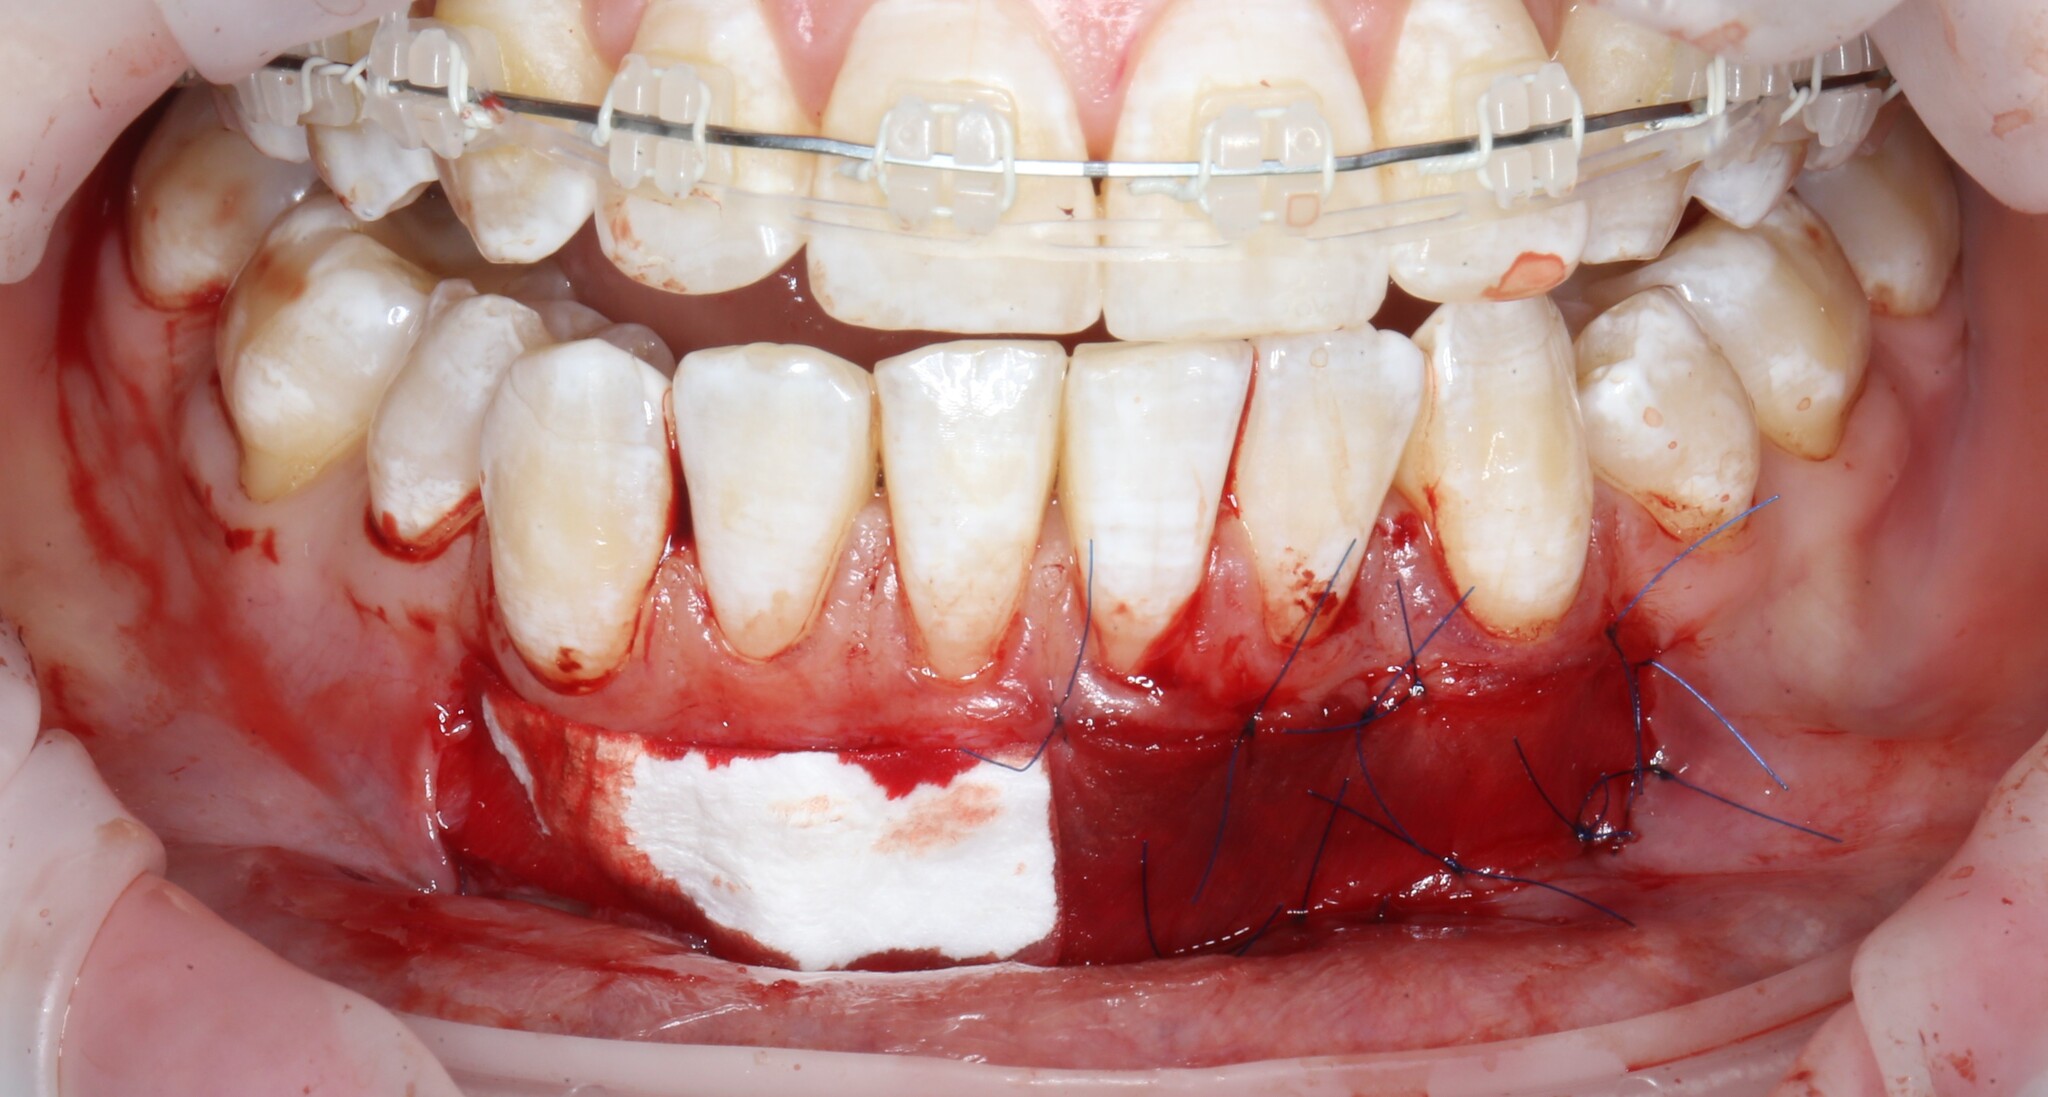

И с другой:

Операция закончена – ничего сложного нет:

Правда, от количества швов меня трясет. Если вам когда-нибудь было интересно, что в своей профессии я не люблю больше всего, так это наложение швов. Для пациента в этом тоже нет ничего приятного. Швы сильно натирают нижнюю губу - приходится меньше разговаривать и больше молчать.